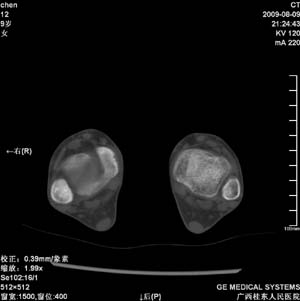

标题: PED2867:右侧内踝肿胀,骨质改变,请各位老师会诊 [打印本页]

标题: PED2867:右侧内踝肿胀,骨质改变,请各位老师会诊

九岁小朋友,近期左侧内踝疼痛,局部肿胀,平时无特殊,近期经常溜干冰

对不起,是右侧内踝肿胀

双踝关节骨质及发育未见异常。